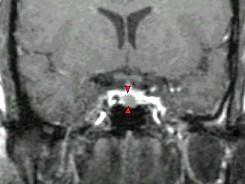

女,38岁,头痛、闭经,MRI检查如图,选择最可能的诊断()A.垂体囊肿B.垂体梗死C.转移瘤D.垂体微腺瘤E.垂体脓肿

问题 女,38岁,头痛、闭经,MRI检查如图,选择最可能的诊断()

选项 A.垂体囊肿 B.垂体梗死 C.转移瘤 D.垂体微腺瘤 E.垂体脓肿

答案 D